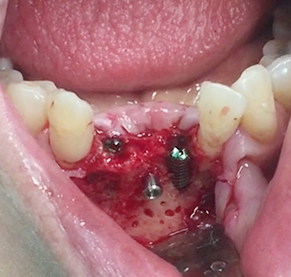

Simultaenous bone grafting for implants

Simultaneous bone graft and implant placement